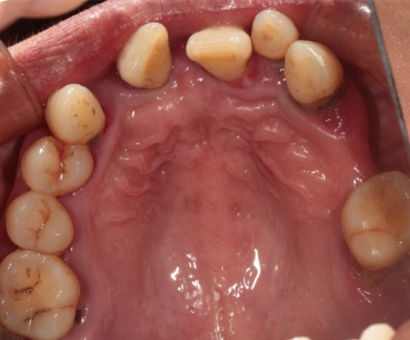

Intraoral Examination(A zone=Right upper jaw、B zone=Left upper jaw、C zone=Left lower jaw、D zone=Right lower jaw)

Poor oral hygiene, accumulation of calculus, three-degree loosening of the entire mouth

Periodontitis causes severe absorption of the upper and lower jaws

A zone A4-A6、B zone B2、C zone C2-C4、D zone D2-D3 lost

A zone A1-A3、A7、B zone B1、B5-B7、C zone C1、C5-C7、D zone D1、D4-D8 all with III°loosen

Photos of preliminary oral diagnosis